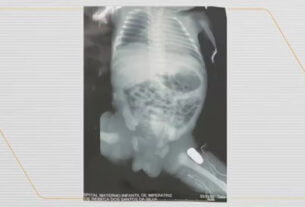

O presidente chegou a São Paulo na madrugada de terça-feira, após ter sentido dores de cabeça. Uma ressonância magnética feita no Hospital Sírio-Libanês, ainda em Brasília, mostrou uma hemorragia intracraniana, decorrente do acidente domiciliar sofrido no dia 19 de outubro. O presidente foi então transferido para a unidade do hospital, na capital paulista, onde passou pelo procedimento cirúrgico.

Na quinta-feira (12), dois dias após a cirurgia, o presidente foi submetido a um novo procedimento, para bloquear o fluxo de sangue e reduzir o risco de formação de novo hematoma. Já na última sexta-feira (13), Lula teve retirado o dreno intracraniano que havia sido colocado na cirurgia da última terça-feira (10). Em um vídeo divulgado nas redes sociais, Lula apareceu caminhando ao lado do neurocirurgião Marcos Stavale.